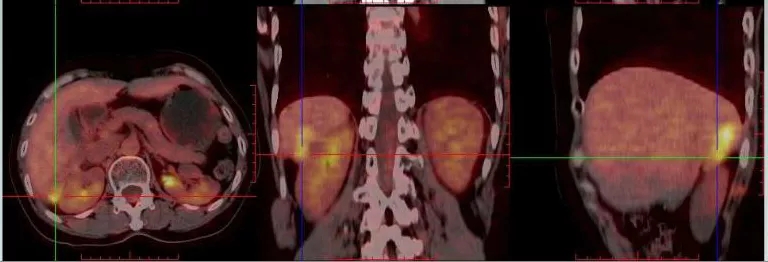

2021.4.23复查CA125上升至70.2U/ml。2021.4.24 CT:肝肾隐窝病灶增大,考虑复发。患者退出BGB-290临床试验。

2021.5.8 PET-CT:肝肾隐窝转移灶。2021.5.12复查CA125水平为95.5U/ml。

PET-CT检查结果